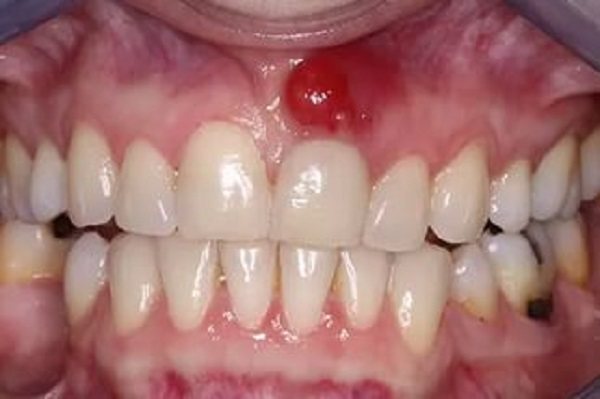

- Цветом – зависит от разновидности нароста. Так, фиброзный идентичен по окрасу с десной, гигантоклеточная – буро-коричневая или синюшная, ангиоматозный – бывает от ярко-красного до темно-красного. Если его часто травмировать пломбой, зубами, протезными кламмерами, его поверхность сильно изъявляется и изменяет окрас.

Ангиоматозное образование

По эстетическим соображениям фото эпулиса на десне не представлены в данной статье. Давайте охарактеризуем ангиоматозную опухоль:

- Внутри образования наблюдается частая сеть мелких кровеносных сосудов.

- Чаще всего встречается у детей 5-18 лет. Группа риска — 5-10 лет.

- Локализация: шейки зубов.

- Внешне напоминает скопление маленьких бугорков. В редких случаях поверхность будет гладкой.

- Цвет опухоли неестественный: ярко-алый, синеватый.

- Основание образования будет плотным и широким.

- Консистенция опухоли твердая и плотная.

- При малейшем повреждении ангиоматозный эпулис начинает кровоточить.

- Опухоль быстро увеличивается в размерах. Кроме того, после ее удаления возможен рецидив.

Ангиоматозный

Представляет собой скопление в фиброзной ткани тучных клеток и кровеносных воспаленных сосудов с очень тонкими стенками. Основная причина его появления – частое травмирование слизистой. Локализуется около зубной шейки и может образовываться на любой челюсти.

Имеет совершенно гладкую или немного бугристую поверхность, красный цвет, мягкую консистенцию, развивается быстро и вызывает сильную кровоточивость даже от незначительного его травмирования. После удаления присутствует большая вероятность его повторного образования.

Разрастание тканей чаще наблюдается у детей, подростков и женщин в период беременности.